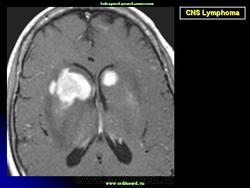

Диагноз подозревается на основе изображений КТ и МРТ.

Лимфома.